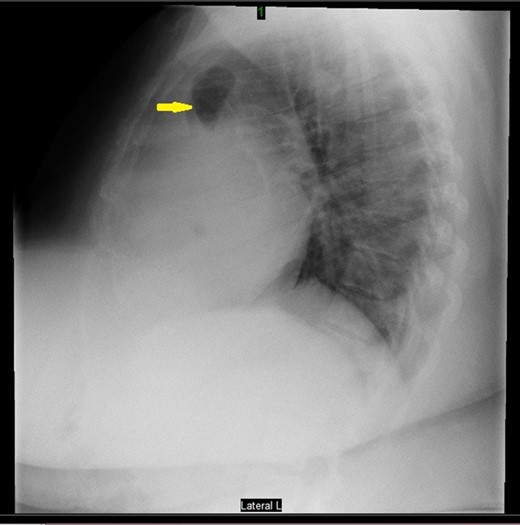

Prior to the surgery patient had symptoms of mild dyspnea, vague abdominal discomfort and an initial evaluation with Chest X Ray revealed bowel gas pattern in the right hemithorax (Fig. 1). A subsequent CAT scan thorax and abdomen revealed a right-sided large morgagni diaphragmatic hernia containing omentum and portion of the transverse colon (Fig. 2). Patient elected to undergo Laparoscopic sleeve gastrectomy and concomitant morgagni diaphragmatic hernia repair. Abdomen was explored laparoscopically which revealed a right sided morgagni diaphragmatic hernia with defect size about 8 × 4 cm, containing omentum, transverse colon and part of the falciform ligament. Contents were reduced successfully taking care not to injure the bowel, falciform ligament partially dissected. A sleeve gastrectomy done. Then the hernial defect was closed primarily by interrupted non absorbable sutures. The closure was then reinforced with a sublay ventralight mesh which was secured using transfascial fixation sutures and with tackers (Fig. 3). The post operative course was unremarkable and the patient was discharged on post operative Day 2 with normal chest X-ray (Fig. 4). At 2 months after surgery the patient was doing well and tolerating solid and liquid diet and no more dyspnea nor GI symptoms.